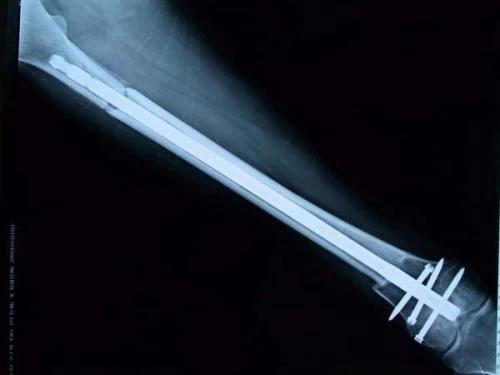

保肢治療指經(jīng)典型骨肉瘤在多學(xué)科團(tuán)隊(duì)醫(yī)生共同努力下完成的新輔助化療、保肢手術(shù)和輔助化療等一系列治療總稱,其目的是在提高患者生存率的前提下,減少局部復(fù)發(fā)、盡量保留良好的肢體功能。肢體經(jīng)典型骨肉瘤保肢治療方法如下圖所示: